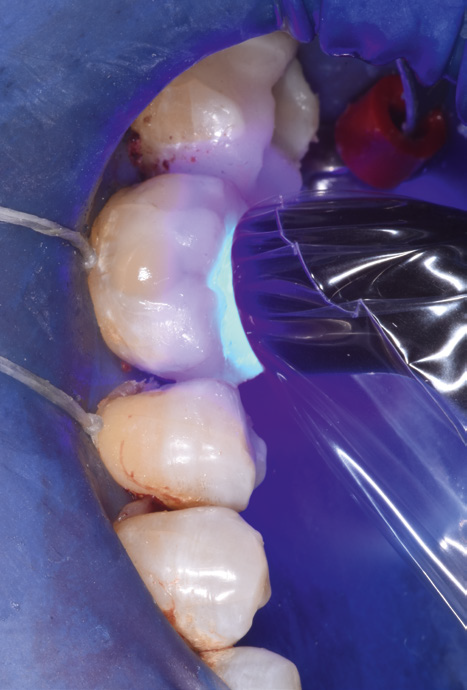

Close-up of a dental procedure showing a molar with blue dental material applied, surrounded by a rubber dam and metal clamp. The focus is on tooth restoration.

Selective enamel etching.